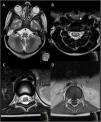

Medulomielorradiculitis, corte axial. Las imágenes ponderadas en T2 mostraron 2 focos hiperintensos simétricos en el bulbo raquídeo posterior (flechas en A) y confirmaron la afectación selectiva de las astas anteriores de la médula espinal, que se muestra a nivel cervical (flechas en B) y del cono medular (flechas en C), con captación en las raíces ventrales de la cauda equina en la imagen axial en la secuencia T1 tras la administración de contraste (flechas en D).